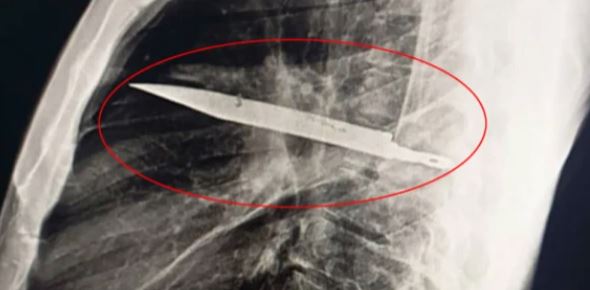

شہری کو سینے میں چبھن کی شکایت، معائنے میں ڈاکٹر وجہ جان کر حیران رہ گئے

حال ہی میں تنزانیہ میں ایک شہری کے سینے سے ایک چاقو نکالا گیا جو 8 سال سے پھنسا ہوا تھا اور چبھن کا سبب بنا ہوا تھا۔ایک 44 سالہ تنزانیائی شہری نے اسپتال کا رخ اس وقت کیا جب اس کے سینے کی دائیں جانب سے پیپ خارج ہو رہی تھی۔ اسے سینے میں درد، سانس لینے میں دشواری، بخار یا کھانسی کا کوئی احساس نہیں تھاڈاکٹروں نے ایکس رے کیا تو سینے کے اندر ایک بڑا چاقو موجود پایا، جو شاید اس کے دائیں کندھے کی ہڈی میں داخل تھا لیکن حیرت انگیز طور پر کسی اہم اعضا کو نہیں چھیڑا تھا۔مریض نے بتایاکہ تقریباً آٹھ سال پہلے ایک پرتشدد جھگڑے کے دوران اسے چوٹیں آئیں۔ اس وقت زخموں کا صرف ابتدائی علاج ہوا مگر چونکہ کوئی شدید تکلیف نہ ہوئی، اس لیے ریڈیولوجی ایکسرے نہیں کروایا گیا۔آپریشن کے ذریعے چاقو کو احتیاط سے نکالا گیا اور ساتھ ہی مردہ بافتوں اور پیپ کی صفائی بھی کی گئی۔ مریض نے 24 گھنٹے آئی سی یو میں گزارے پھر عمومی وارڈ میں 10 دن داخل رہا۔طبی جرنل میں شائع یہ غیرمعمولی کیس شائع ہوا جس میں ڈاکٹروں نے اس واقعے کو انتہائی نایاب واقعہ قرار دیا۔